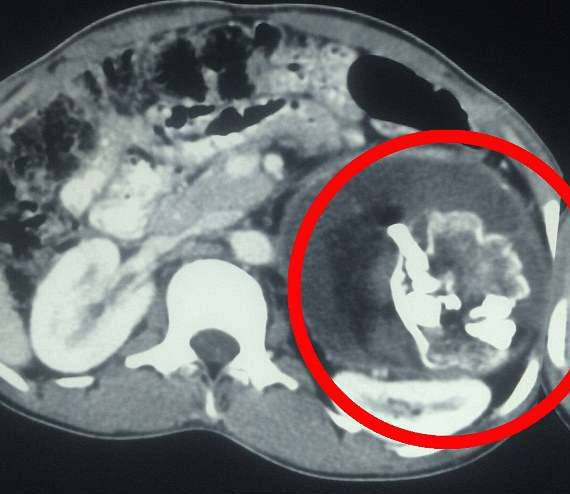

▼手术时医生才知道,异物就是「寄生胎」。

▼从医学角度来讲,这个胎儿还活着。

寄生胎是孪生胚胎发育时产生的特别现象。一个胚胎进入另一个胚胎中,像寄生虫一样,吸收宿主的养分生长。从医学角度来看,这个寄生胎还活着。手术后库马尔的身体状况逐渐好转,他的父亲表示,多年来的噩梦终于解脱,儿子很快就能回到学校,正常生活,这是最值得开心的事。

▼异物是个发育不完全的头颅,上面有头髮和牙齿。